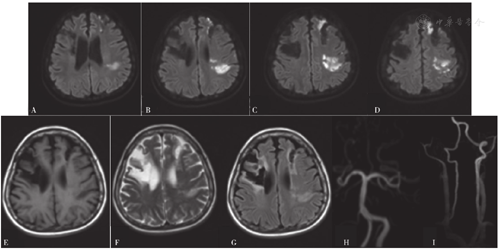

2019-01-02,患者因"右侧肢体无力2 d"而又一次入住滨州医学院附属医院(距离上次住院时间为1年2个月)。患者入院前2 d无明显诱因出现右侧肢体无力,上肢不能抬起及持物,下肢行走拖曳,为求系统诊疗而就诊于滨州医学院附属医院,门诊以"脑梗死"收入院。查体:血压为133/74 mm Hg,心率为127次/min,意识清,言语流利,伸舌偏右,右侧上肢肌力为0级、肌张力减低,右侧下肢肌力为3级、肌张力正常,双侧腱反射(+++),右侧指鼻试验及跟膝胫试验不合作,双侧Babinski征(+),双侧Chaddock征(+),下腹部可见一长约12 cm的剖宫产手术瘢痕、无渗血、渗液、切口愈合可,NIHSS评分为7分。颅脑MRI检查结果:左侧额叶、左侧顶叶急性脑梗死灶;双侧额叶、右侧放射冠软化灶;头颈部MRA检查结果:双侧颈内动脉及右侧大脑前动脉、右侧大脑中动脉未见显影(见图3),考虑闭塞、烟雾病?建议行头颈部CTA或DSA。颈动脉、椎动脉及双侧锁骨下动脉超声检查结果:右侧颈动脉内中膜不均匀增厚;左侧颈内动脉中远端闭塞或极重度狭窄;右侧颈内动脉起始段以远闭塞或极重度狭窄;双侧颈外动脉、双侧椎动脉、双侧锁骨下动脉均呈明显低阻力频谱。TCD检查结果:双侧颈内动脉严重狭窄或闭塞不除外(右侧为著,右侧眼动脉侧支循环开放);左侧大脑中动脉近端或颈内动脉末端及大脑前动脉狭窄;左侧大脑后动脉狭窄或代偿性改变;右侧椎动脉狭窄不除外;可能符合烟雾病TCD改变。甲状腺彩超检查结果:甲状腺弥漫性病变,血流丰富,流速增高。脑DSA检查结果:左侧颈内动脉近端萎缩变细,远端止于眼动脉,显影延迟;右侧颈内动脉发出1 cm后闭塞;左侧后交通动脉开放,供血左侧颈内动脉末端及左侧大脑中动脉、大脑前动脉,显影略延迟;右侧大脑后动脉发出分支,供血右侧大脑中动脉区(见图4)。心电图检查结果:窦性心动过速。甲状腺功能指标:游离三碘甲状腺原氨酸为10.28 pmol/L,游离甲状腺素为28 pmol/L,促甲状腺激素<0.005 mU/L,抗甲状腺球蛋白抗体为146.4 U/ml,甲状腺过氧化物酶抗体为56.7 U/ml。

注:A示右侧颈内动脉闭塞,B~C示左侧颈内动脉近端萎缩变细、远端止于眼动脉,D~E示右侧大脑后动脉发出分支并供血右侧大脑中动脉区